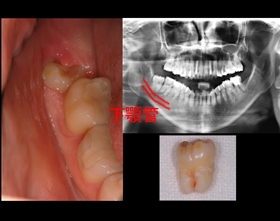

親知らず

親知らず:口腔内写真とパノラマXray写真(2次元) 親知らず:CT画像(3次元)

口腔内写真とパノラマXray写真(2次元)

CT画像(3次元)

親知らずは下顎管(血液と神経の通路)に近接している為、抜歯は注意しておこなわなければなりません。

CT撮影をすることにより下顎管と歯の距離を正確に確認出来ます。